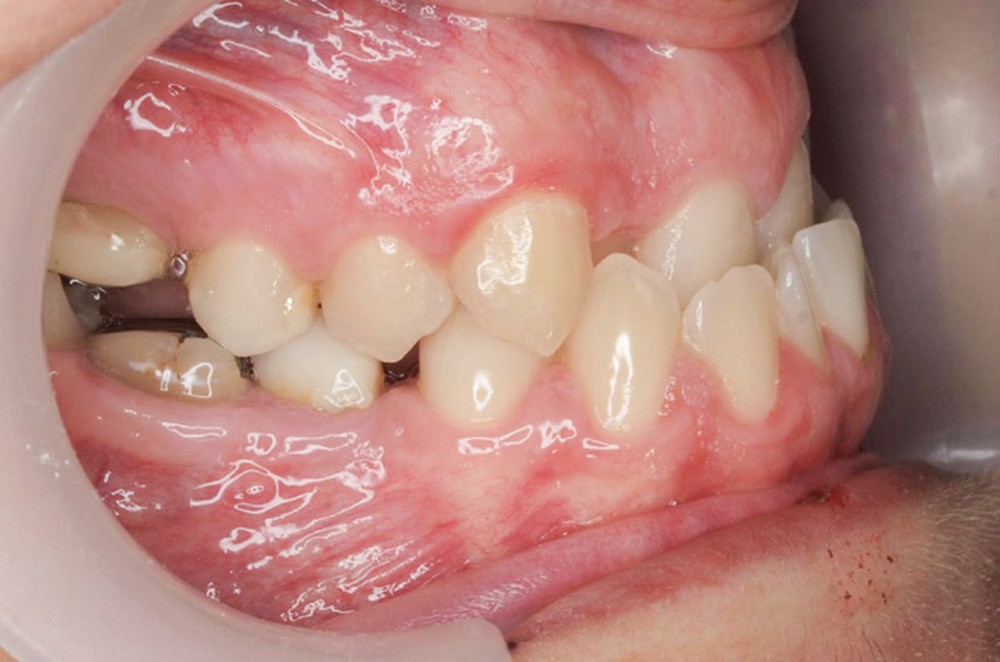

Diagnostic (fig. 1a-g)

La patiente présente une classe III squelettique dans un contexte hyperdivergent associée à une endoalvéolie maxillaire, un articulé inversé antérieur, une rétroversion incisive maxillaire, des rapports de classe I canine bilatérale, une absence de 16 et 36.

Au niveau esthétique, le profil est rectiligne. La lèvre supérieure est plus effacée, en retrait par rapport à la lèvre inférieure. De face et de profil, la mandibule paraît massive et le maxillaire effacé : le manque de soutien de la lèvre supérieure contribue à cette impression.

Le sourire est étroit, dégradé par les malpositions dentaires.

Au niveau fonctionnel, il existe un pro-glissement mandibulaire et un articulé inversé antérieur. Le profil téléradiographique montre en occlusion des rapports labiaux et un profil de classe III plus marqué que sur photographies.